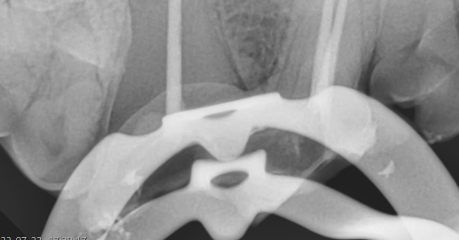

ラバーダム防湿

歯髄(歯の神経)を触る治療時の必須アイテムです。

人の歯科医院でも付加価値のある治療に使われています。

ゴムのシートを治療する歯に被せ、歯が唾液に触れることを防ぎます。

抜髄をする際にはラバーダム防湿を行うことで有害な洗浄液が正常組織に触れることを防ぎ、歯内をしっかりと洗浄殺菌できることから治療の成功率が上がります。

犬歯治療時の装着例

奥歯の装着例

実際の治療時